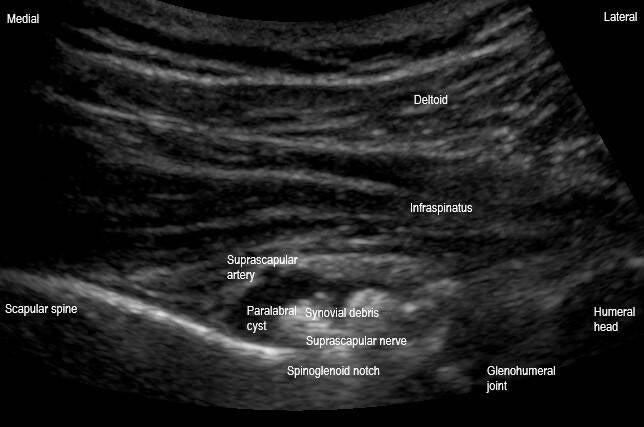

This is a transversal plane view of the spinoglenoid notch of the scapula. This image demonstrates a cystic lesion within the spinoglenoid notch containing hypoechoic and echogenic material compressing the suprascapular nerve deep in the notch. This is most consistent with a complex paralabral cyst of the spinoglenoid notch. This can be a cause of suprascapular nerve entrapment and neuritis, as was the case in this patient.